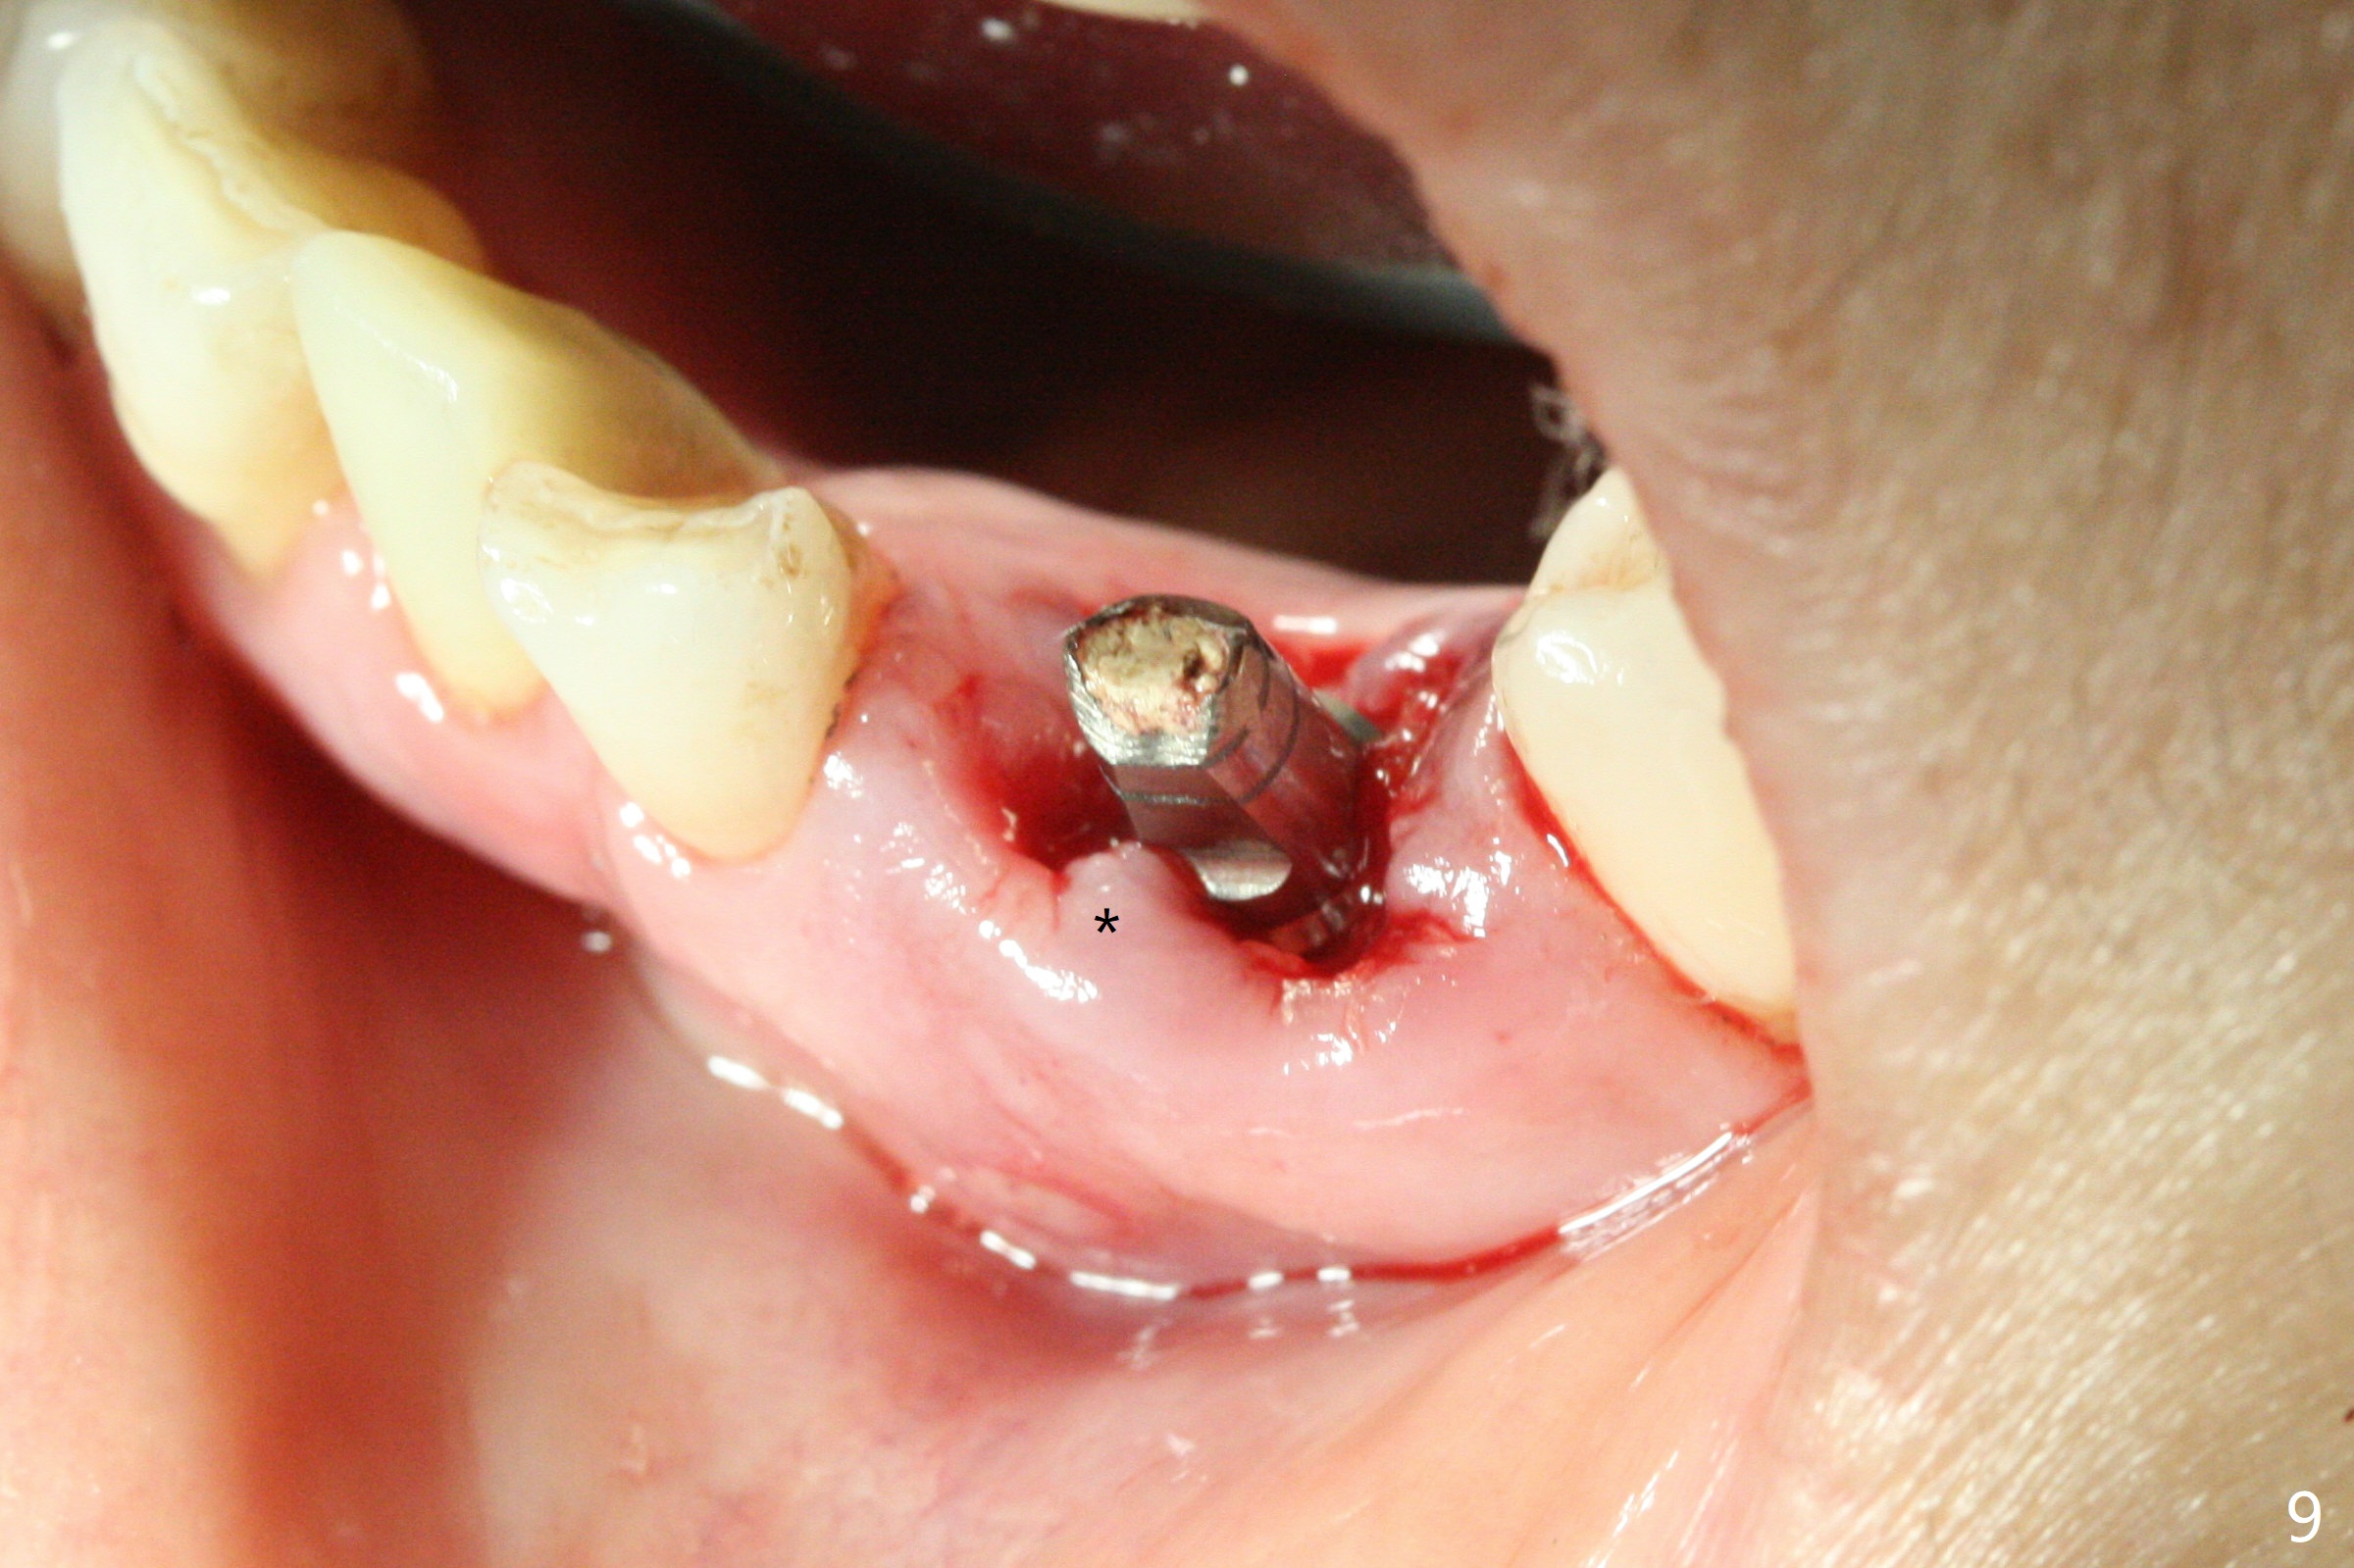

There is a fistula buccal to the apex of the tooth #23 preoperatively (Fig.1), which is related to loss of the buccal plate of the socket of #23. Therefore an implant is placed mainly in the socket of #22 (Fig.3). The lingual (Fig.2 L) gingiva appears to have more extensive inflammation. After extraction, the lingual (Fig.3 L) gingival margin is significantly lower than the buccal one. The lingual crest is ~ 4 mm lower than the buccal one. A 3.8x10 mm dummy implant is placed tentatively with an apical space (Fig.4). When a same dimension definitive implant is placed with 40 Ncm, it is 2 mm below the lingual gingival margin, whereas 6-7 mm below the buccal one (Fig.5). Vanilla graft is placed before placement of a 5.5x4(5) mm abutment (Fig.6,7). There is a 2-3 mm lingual (L) gap to be filled with the allograft secondarily to prevent periimplantitis (Fig.7). Later the abutment is changed to a longer and smaller one (Fig.8) with more of the allograft (*). After trimming of the abutment (Fig.9 (*: papilla between the fused teeth)), an immediate provisional is fabricated to close the socket (Fig.10, similar to Fig.1). The majority of the bone graft seems to be in place 8 months postop (Fig.12). The implant appears to have been placed buccal, consistent with the thin and slightly erythematous buccal gingiva (Fig.13). The ridge completely regenerates 2 years post cementation (Fig.14).